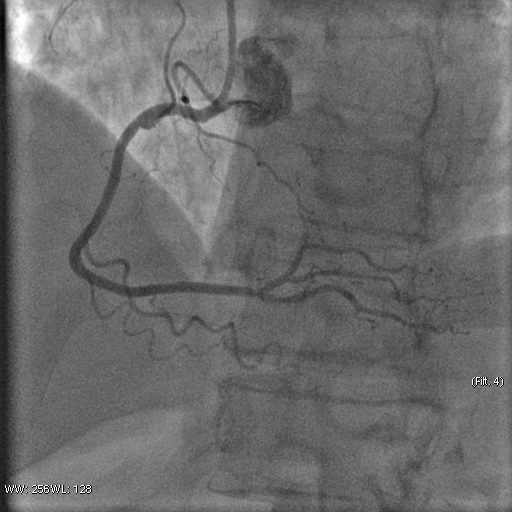

Stenosis of the anterior interventricular artery in the 6.7 segment is 95%. Stenosis of the orifice of the diagonal artery of the 1st order is 95%. Stenosis of the circumflex artery in the 13th segment is 40%. During coronary angiography, pronounced spasm is noted in the 2nd segment of the right coronary artery with complete occlusion of the artery lumen. After stopping the spasm, coronary angiography shows a spiral (spontaneous) dissection of the right coronary artery from segments 1 to 3.

A guiding catheter JR 3.5 6Fr was inserted along a 0.035" 260.0 cm guidewire. The guidewire was removed. The right coronary artery was catheterized. A 7Fr Y-click connector (complete with an insertion device and a guidewire rotation device) was connected to the guiding catheter. A coronary guidewire Whisper ES 0.014" 190 cm, Asahi Gaia Third 0.014" 190 cm was inserted and brought into the orifice of the right coronary artery. The guidewire was inserted beyond the lesion zone of the right coronary artery in segment 2, then into the distal sections. Wilma NC 2.00*20.0 mm and Wilma NC 3.00*15.0 mm balloon catheters were inserted alternately along the coronary guidewire - predilation of the lesion zone of the right coronary artery in segment 2 was performed. Inflation of balloon catheters 14 atm. with an inflator, the balloon catheters are deflated and removed. A stent is inserted along the coronary guidewire - the Yukon Chrom PC 3.0 * 28.0 mm system, Yukon Chrom PC 3.0 * 28.0 mm, Cid Cre 8 3.50 * 25.0 mm, Cid Cre 8 4.0 * 16.0 mm - the stent is implanted in the lesion area of the right coronary artery in the 2nd segment. Inflation of the balloon catheter 9-16 atm. with an inflator, the balloon catheter is deflated and removed. Control coronary angiography - blood flow in the stenting zone is TIMI3, there are no signs of dissection or stent dislocation.